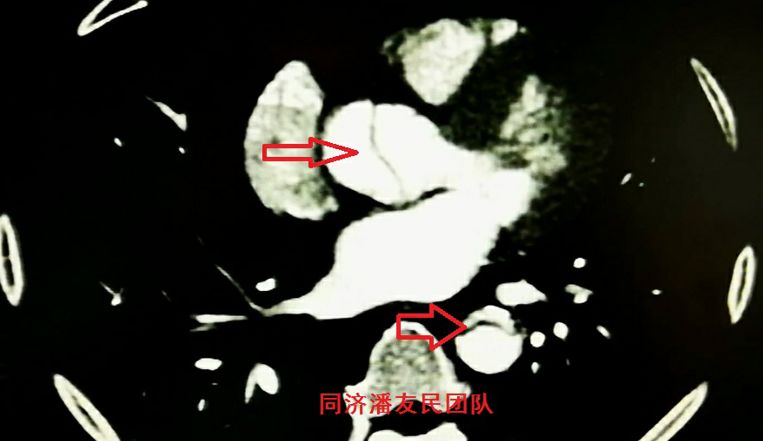

结果在上级医院复查胸腹主动脉CTA,在平扫CT提示主动脉夹层的对应层面,证实了主动脉夹层(图3~6)。同时发现升主动脉及主动脉弓均有夹层撕裂 (图7~8) 。 因此,正确诊断应该是 A型 (1型) 主动脉夹层。

图8:CTA显示升主动脉及胸降主动脉均有夹层撕裂内膜片(红箭头所示)

腹腔干动脉由真假双腔供血,真腔狭窄(图9),肠系膜上动脉由假腔供血,真腔完全压闭了(图10),双肾动脉也由假腔供血(图11)。由于腹腔脏器缺血导致脾脏、左肾部分梗死。因此,患者主要症状是腹痛,而胸痛不明显。这可能也是导致诊断分型不准确的原因之一。